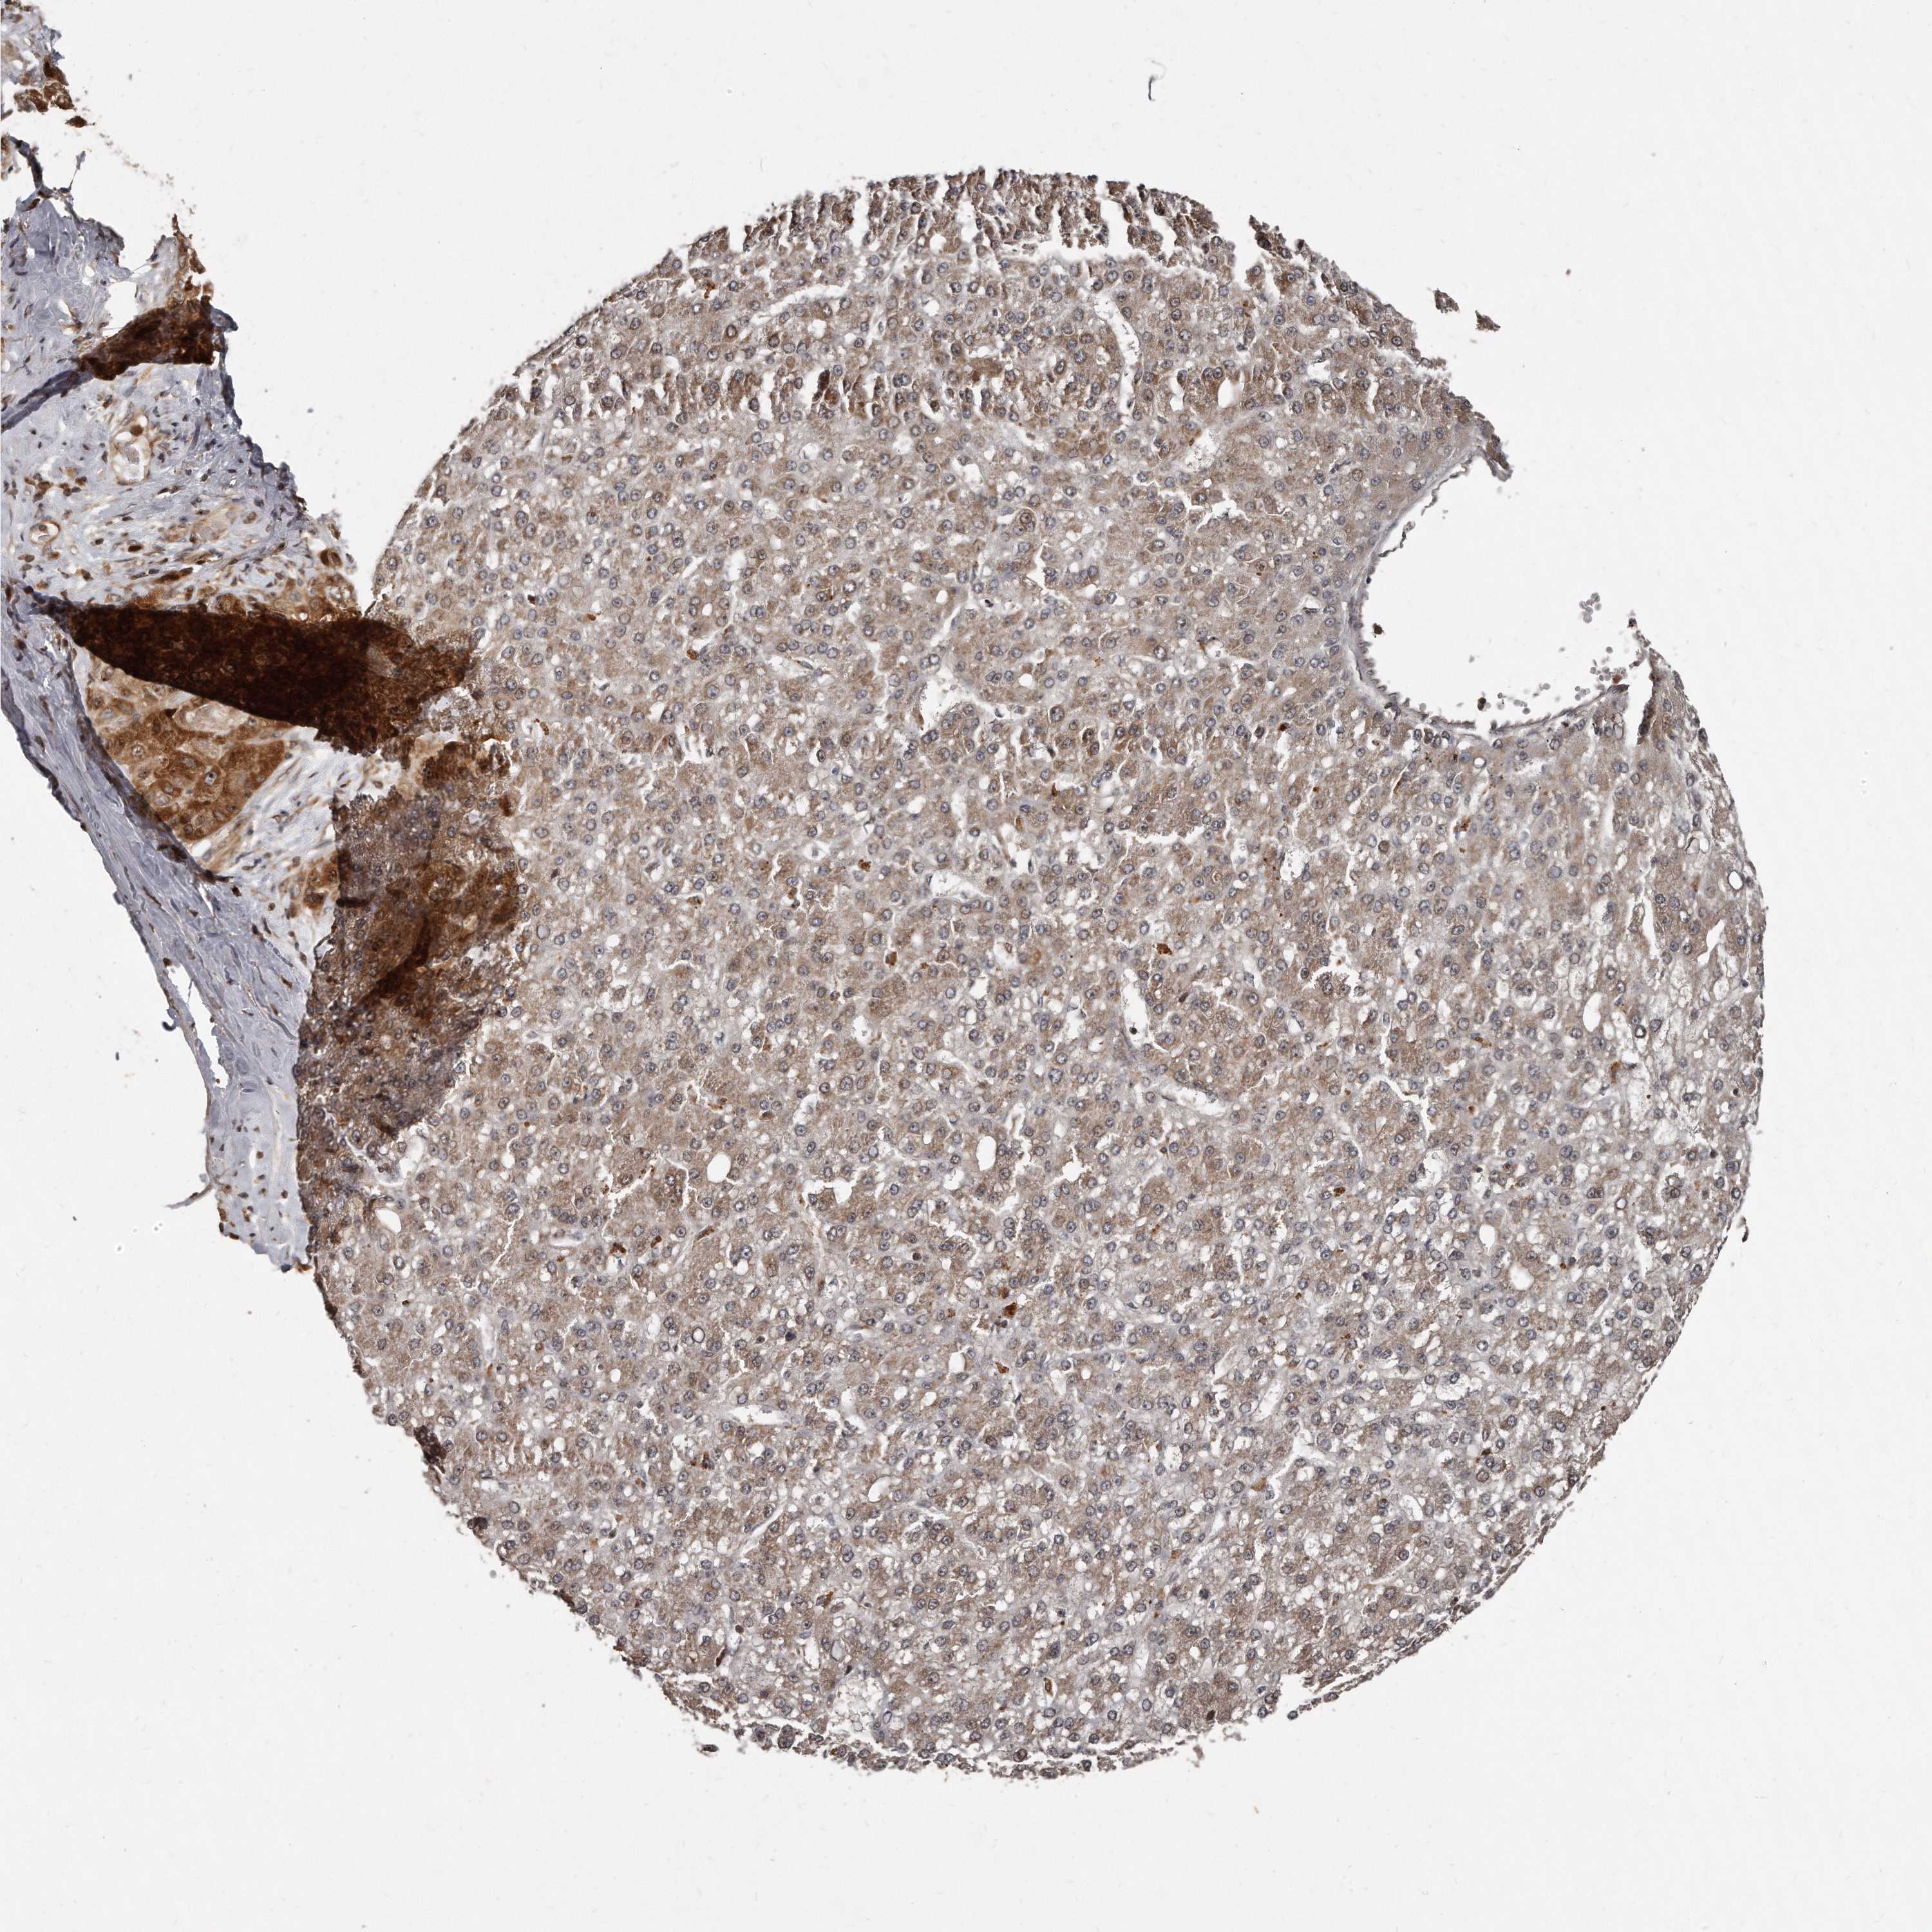

LIVER CANCER - Protein expressioni

A mouse-over function shows sample information and annotation data. Click on an image to view it in a full screen mode. Samples can be filtered based on level of antibody staining by selecting one or several of the following categories: high, medium, low and not detected. The assay and annotation is described here.

Note that samples used for immunohistochemistry by the Human Protein Atlas do not correspond to samples in the TCGA dataset.

Antibody stainingi

Antibody staining in the annotated cell types in the current human tissue is reported as not detected, low, medium, or high, based on conventional immunohistochemistry profiling in selected tissues. This score is based on the combination of the staining intensity and fraction of stained cells.

Each image is clickable and will lead to virtual microscopy that enables deeper exploration of all samples and also displays staining intensity scores, fraction scores and subcellular localization as well as patient and tissue information for each sample.

Antibody HPA028612

Staining

High

Medium

Low

Not detected

Intensity

Strong

Moderate

Weak

Negative

Quantity

>75%

75%-25%

<25%

None

Location

Nuclear

Cytoplasmic/membranous

Cytoplasmic/membranous,nuclear

Cholangiocarcinoma

Carcinoma, Hepatocellular, NOS